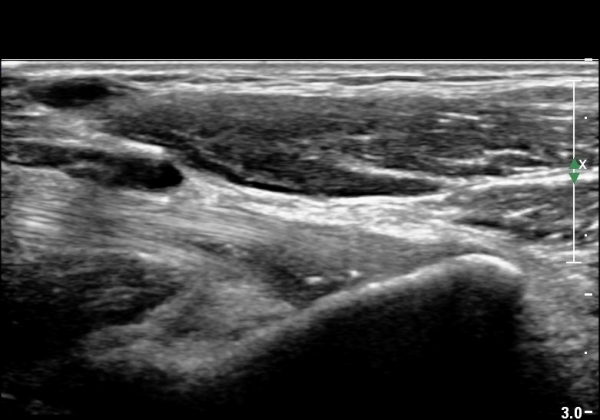

¿ìÃø ÆÈ²ÞÄ¡ ¾ÕÂÊ¿¡¼­ ÀÌµÎ¹Ú±Ù°Ç È¾´Ü¸é°Ë»ç¿¡¼­ À̵ιڱٰǿ¡ ƯÀÌ ¼Ò°ßÀ» º¸ÀÌÁö ¾Ê(±×¸² 1, 2).